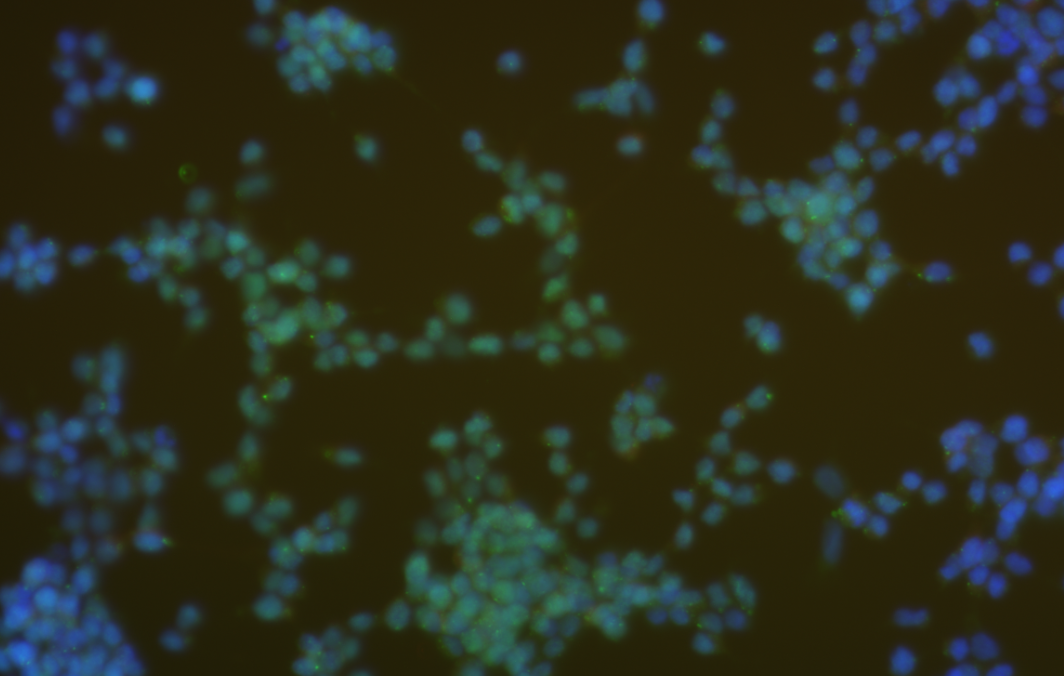

FISH是一种基于荧光原位杂交技术的核酸探针检测方法。它利用特定的核酸探针与细胞中的DNA或RNA序列进行杂交,然后通过荧光显微镜观察和分析荧光信号。FISH主要用于检测基因或染色质异常、染色体变异等遗传学问题,也可用于肿瘤诊断和预后评估等。

FISH利用特定的核酸探针进行标记,这些探针可以与目标DNA或RNA序列特异性结合,常见的探针标记物包括荧光染料、量子点等。

FISH的观察和分析同样通过荧光显微镜进行,可以观察探针与目标序列的杂交情况以及荧光信号的强度和分布,从而对染色体变异、基因表达等问题进行分析。

FISH的灵敏度和特异性也较高,可以检测出单个基因的表达情况,并且可以针对特定的基因或染色体区域进行多重检测。